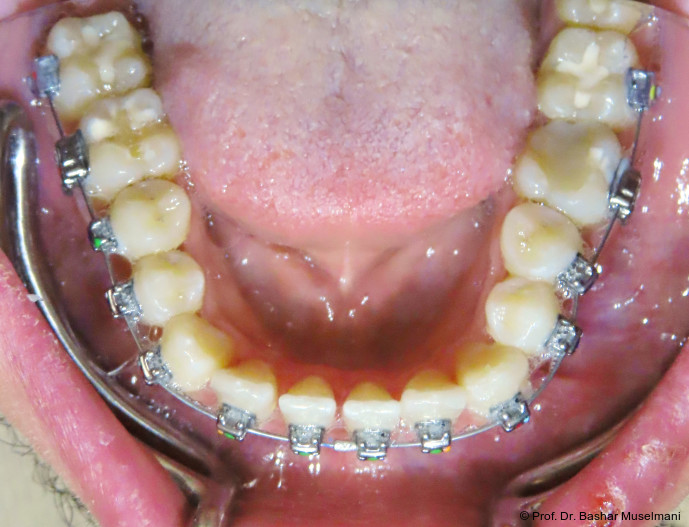

Die Abbildungen 1 bis 3 zeigen die initiale klinische und radiologische Ausgangssituation.

Apparative Versorgung

Die Behandlung erfolgte mittels einer festsitzenden Multibracketapparatur unter Verwendung passiver selbstligierender Brackets (Damon Ultima System) im Ober- und Unterkiefer.

Unterkiefer

• Zähne 33–43: Brackets mit proklinationsförderndem Torque

Hierdurch sollte eine gezielte Proklination der unteren Front zur Verbesserung des Overjets und der sagittalen Verzahnung erreicht werden.

Zu Beginn der Nivellierungsphase wurden in beiden Kiefern 0.013" CuNiTi-Bögen eingesetzt (Abb. 4a–e).